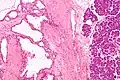

![]() | |

Micrograph showing a pancreatic serous cystadenoma. H&E stain. | |

Pathologists classify serous cystic neoplasms into two broad groups. Those that are benign, that have not spread to other organs, are designated "serous cystadenoma".[5] Serous cystadenomas can be further sub-typed into microcystic, oligocystic (or macrocystic), solid, mixed serous-endocrine neoplasm, and VHL-associated serous cystic neoplasm. This latter classification scheme is useful because it highlights the range of appearances and the clinical associations of these neoplasms. Serous cystic neoplasms that have spread ("metastasized") to another organ are considered malignant and are designated "serous cystadenocarcinoma".

Pathology